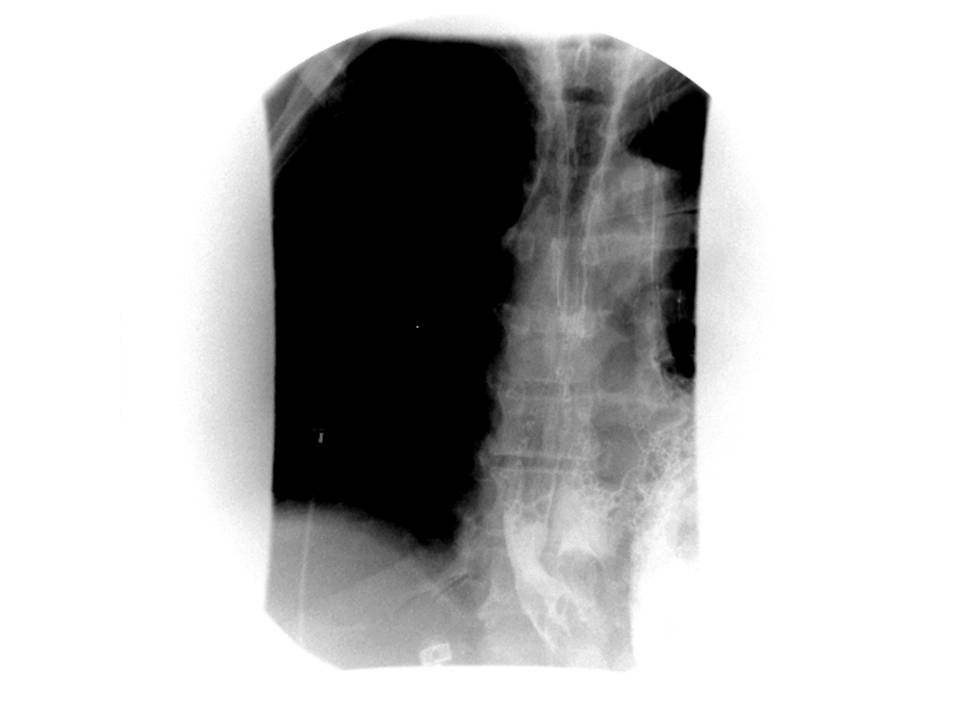

In the present case, esophagogram with water-soluble contrast agent revealed leakage of contrast from the distal esophagus to the pleural space, confirming the diagnosis of esophageal rupture. The esophagogram with water-soluble contrast showing contrast in the distal esophagus, mediastinum, and pleura is shown in Figure 3.